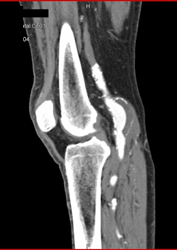

Popliteal Artery Aneurysm